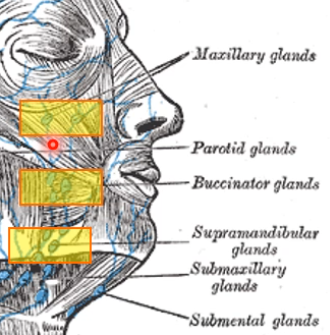

Lymphatic system

總圖

Nodes

Face

- Maxillary

- Buccinator

- Supramadibular